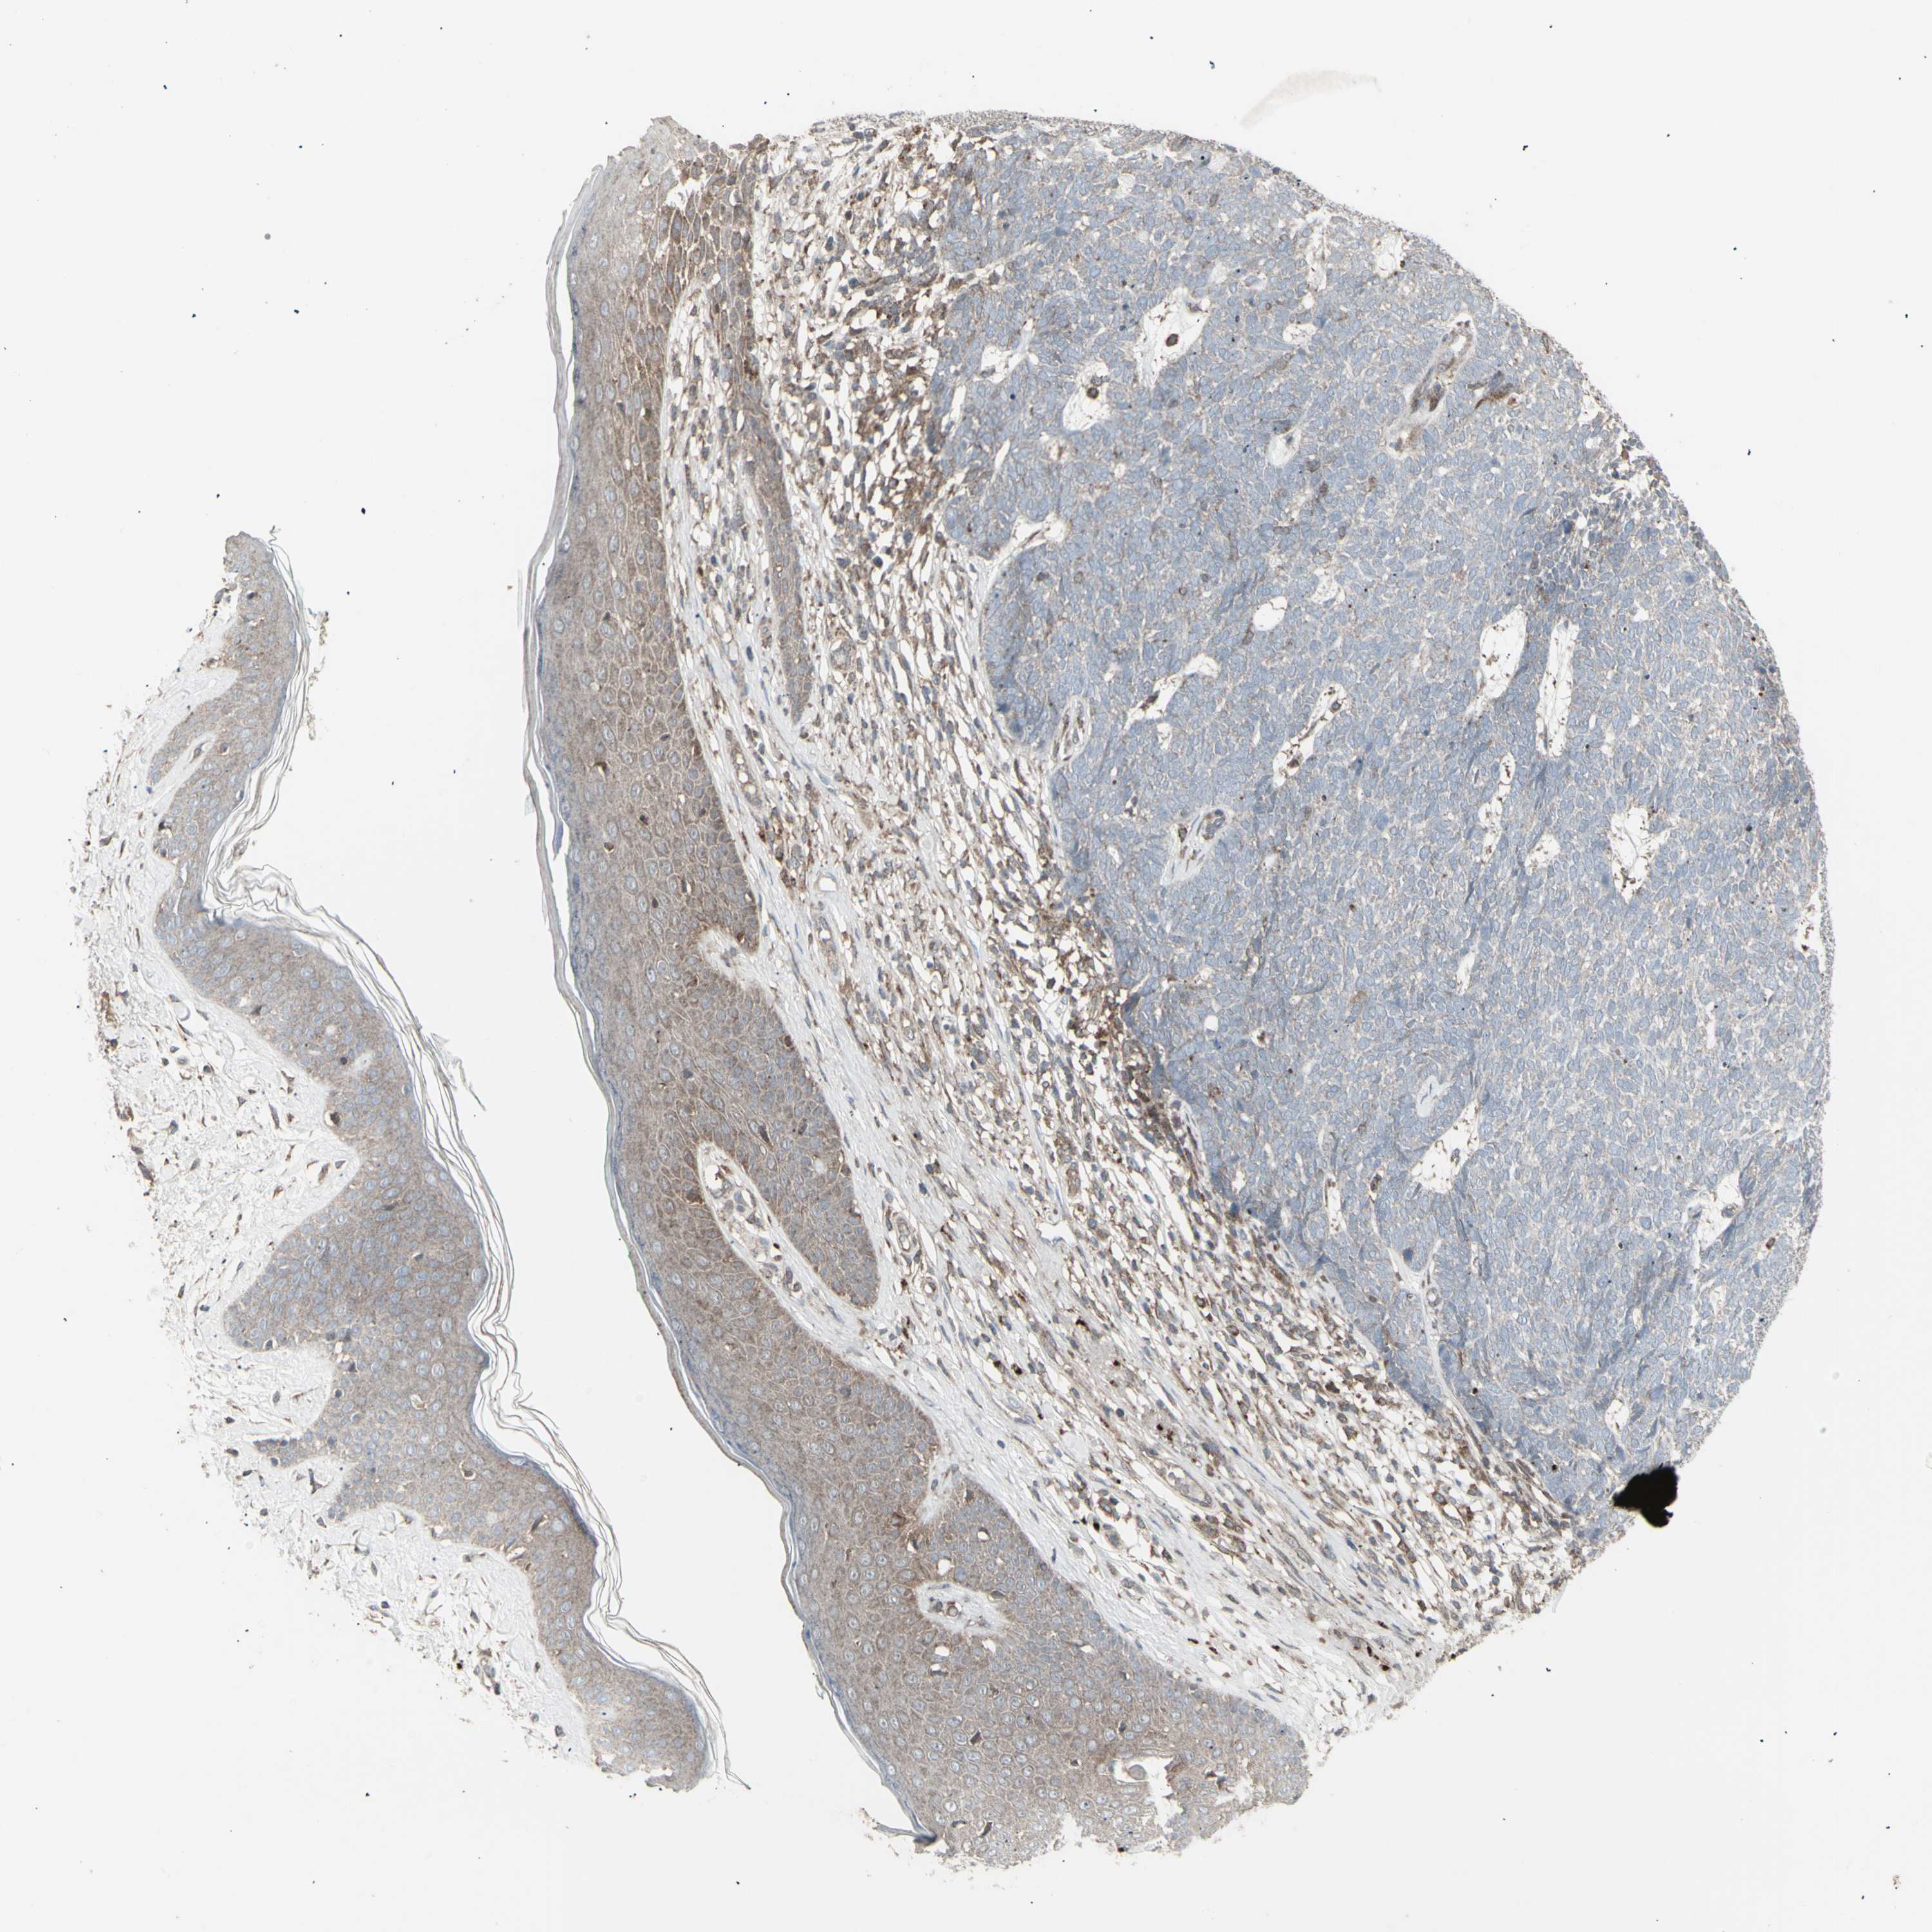

SKIN CANCER - Protein expressioni

A mouse-over function shows sample information and annotation data. Click on an image to view it in a full screen mode. Samples can be filtered based on level of antibody staining by selecting one or several of the following categories: high, medium, low and not detected. The assay and annotation is described here.

Antibody staining in the annotated cell types in the current human tissue is reported as not detected, low, medium, or high, based on conventional immunohistochemistry profiling in selected tissues. This score is based on the combination of the staining intensity and fraction of stained cells.

Each image is clickable and will lead to virtual microscopy that enables deeper exploration of all samples and also displays staining intensity scores, fraction scores and subcellular localization as well as patient and tissue information for each sample.

Antibody HPA002633

Antibody HPA046758

Antibody CAB010906

Squamous cell carcinoma, NOS

Basal cell carcinoma